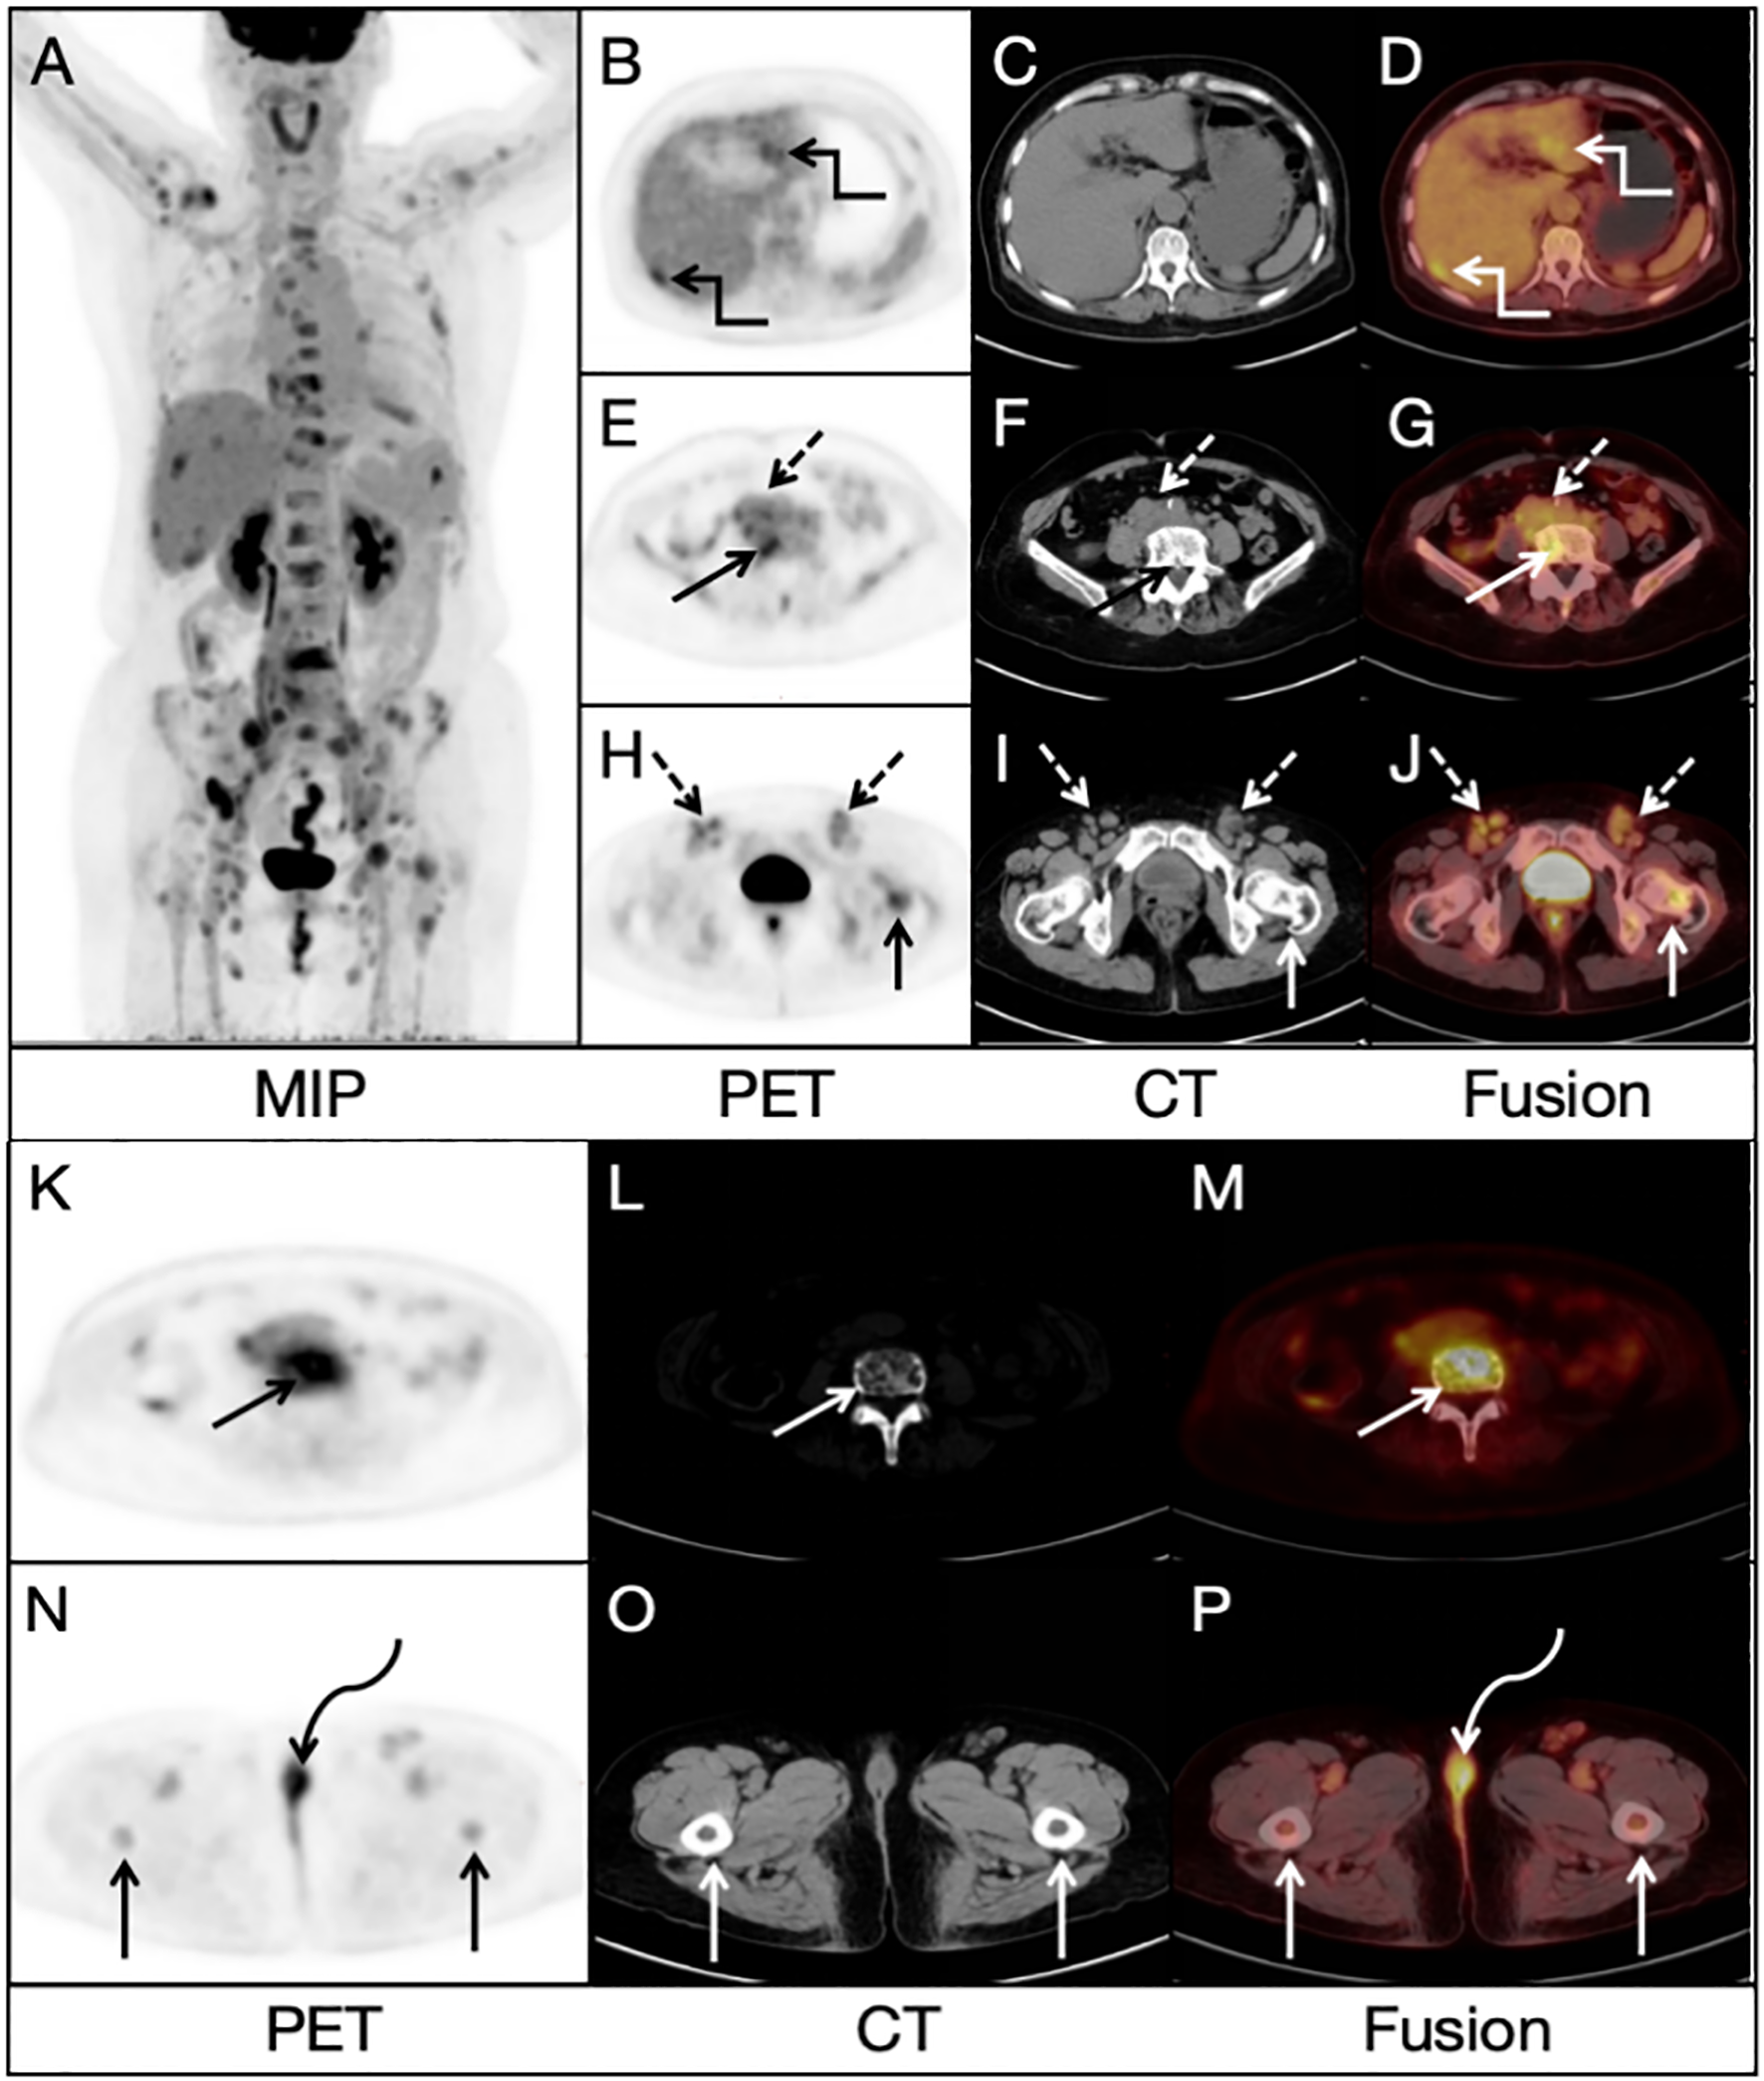

A 68-year-old woman presented with low back pain for 1 month, and a non-contrast-enhanced abdominal CT revealed several lesions on her spine bones, suggesting multiple metastatic lesions. Furthermore, laboratory examinations showed increased tumor markers: CA125: 50.7 U/ml (normal value < 35 U/ml), Ferritin: 539 ng/ml (normal value 13-150 ng/ml). This patient had no previous history of malignancy. For evaluating the general condition, this patient underwent 18F-FDG PET/CT imaging, which demonstrated multiple fluorodeoxyglucose (FDG) uptake in the liver, bones and lymph nodes in the PET/CT MIP image (Figure 1A). Multiple foci of abnormal activity (broken arrows) were seen in the liver (Figures 1B, D), although there was no clear evidence of anatomical abnormality in the corresponding CT image (Figure 1C). Multiple hypermetabolic foci (solid arrows) were also seen in the bones (Figures 1E–P), with mixed bone destruction on CT (Figure 1L). Enlarged retroperitoneal and bilateral inguinal lymph nodes (dashed arrows) with increased activities were seen on PET/CT (Figures 1E–J). An additional focal activity (Figures 1N, P, curved arrows) with SUVmax of 6.2 was also observed in the vulva, although CT indicated no clear evidence of anatomical abnormality in the corresponding area (Figure 1O).

Figure 1. Radiological findings on 18FDG PET/CT image: (A) Multiple lesions in the bones, liver and lymph nodes. (B, D) Multiple foci of abnormal activity (broken arrows) in the liver. (C) No clear evidence of anatomical abnormality in the corresponding area on CT image. (E–J) Enlarged retroperitoneal and bilateral inguinal lymph nodes (dashed arrows). (K–M) Multiple hypermetabolic foci (solid arrows) in the bones (N, P) An additional focal activity (curved arrows) with a SUVmax of 6.2 in the vulva. (O) No clear evidence of anatomical abnormality in the corresponding area on CT image.